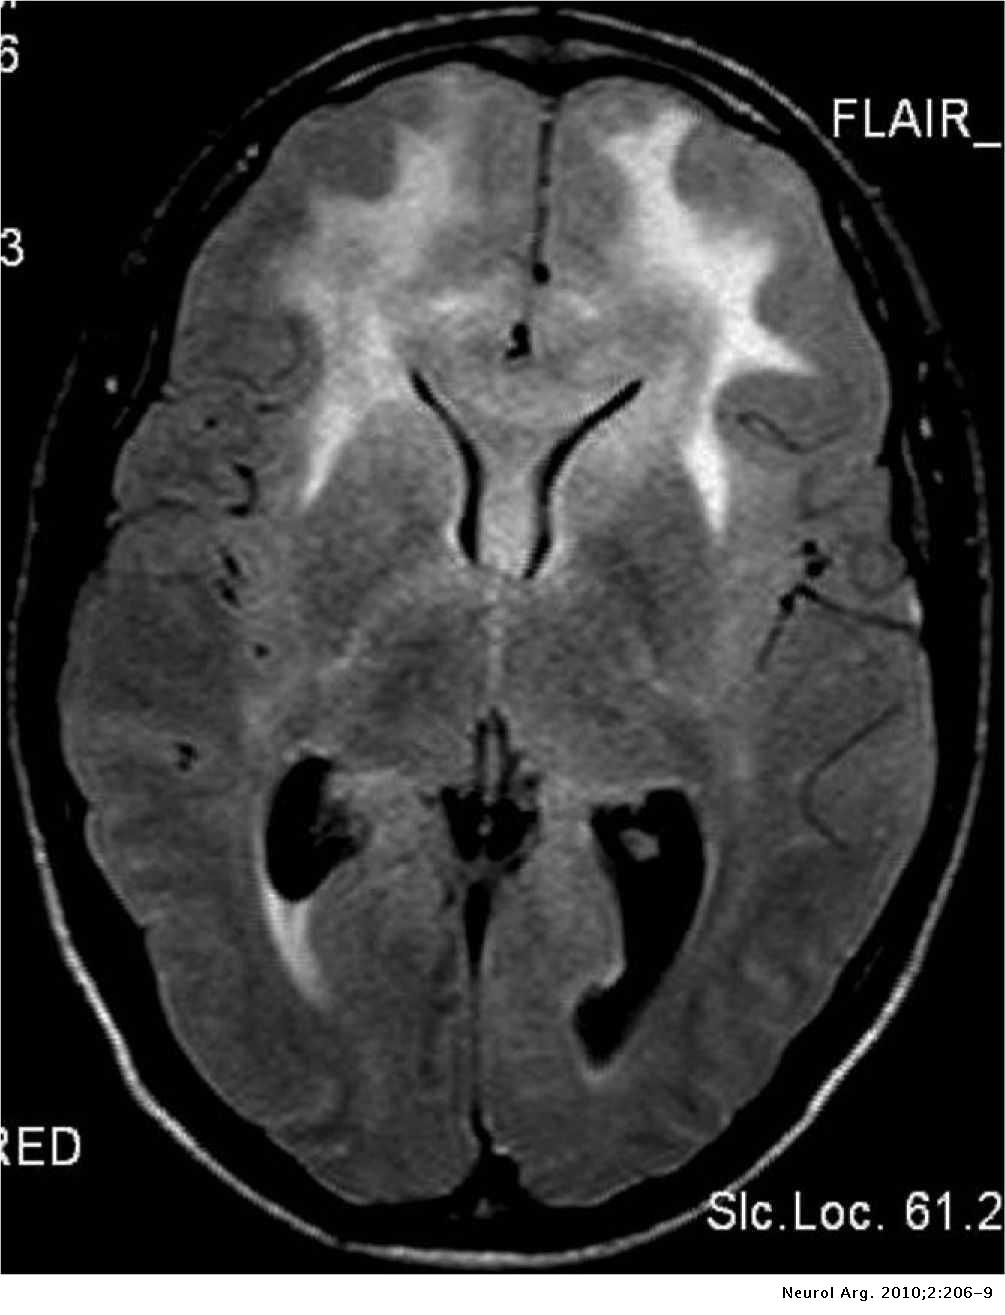

Alla risonanza magnetica la neoplasia appare come una lesione diffusa, poco circoscritta, infiltrante e senza enhancement, con segnale iperintenso nelle immagini pesate T2, e che si espande verso la materia bianca. È difficile da distinguere da un astrocitoma anaplastico altamente infiltrante o da un glioblastoma.